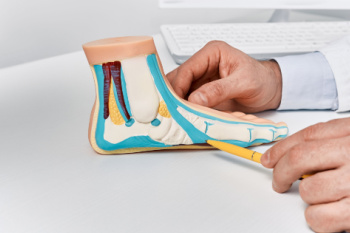

Heel pain is often associated with plantar fasciitis. The plantar fascia is a band of tissues that extends along the bottom of the foot. A rip or tear in this ligament can cause inflammation of the tissue.

Heel spurs are another cause of pain. When the tissues of the plantar fascia undergo a great deal of stress, it can lead to ligament separation from the heel bone, causing heel spurs.

Plantar Fasciitis

One of the main causes of heel pain is a condition known as plantar fasciitis. The plantar fascia is a band of tissue that extends along the bottom of the foot, from the toe to the bottom of the heel. A rip or tear in this ligament can cause inflammation of these tissues, resulting in heel pain. People who do not wear proper fitting shoes are often at risk of developing problems such as plantar fasciitis. Unnecessary stress from ill-fitting shoes, weight change, excessive running, and wearing non-supportive shoes on hard surfaces are all causes of plantar fasciitis.

A third cause of heel pain is a heel spur. A heel spur occurs when the tissues of the plantar fascia undergo a great deal of stress, leading to a separation of the ligament from the heel bone entirely. This results in a pointed fragment of bone on the ball of the foot, known as a heel spur.

Plantar fasciitis is a painful injury. It is inflammation of the plantar fascia, the thick band of tissue running from the heel to the base of the toes. If left untreated, it can lead to a degenerative disease called plantar fasciosis. There are several effective treatments for this ailment. Doctors often prescribe rest, massages, stretching, night splints, physical therapy, anti-inflammatory medication, corticosteroids or surgery, usually in that order. The most effective treatment for plantar fasciitis is orthotics, which offers foot support. Surgery is occasionally used as a last resort, but it comes with the risk of nerve damage and infection and often does not stop the pain.